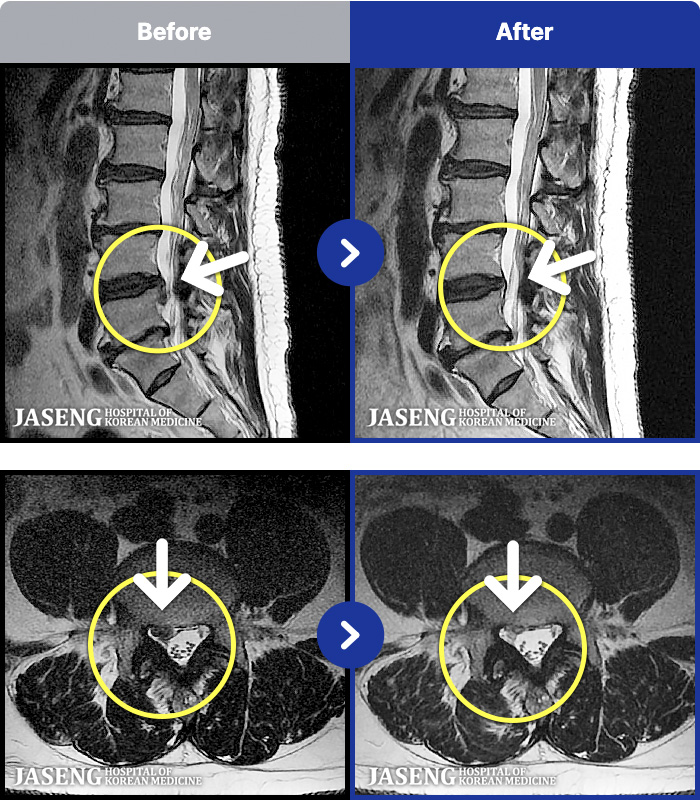

MRI ġ

54 MRI ũ ʸ Ȯϼ.

Ƹ ϰ ־.

ǿ

õ

ȯ

㸮ũ

¥

2025.08.01

ȸ

34,882

[õ] 25.03.18~25.07.22

ȯںп Ǹ ǿ ԿǾ, ο ġ ۿ Ƿ ġḦ Ͻñ ٶϴ.